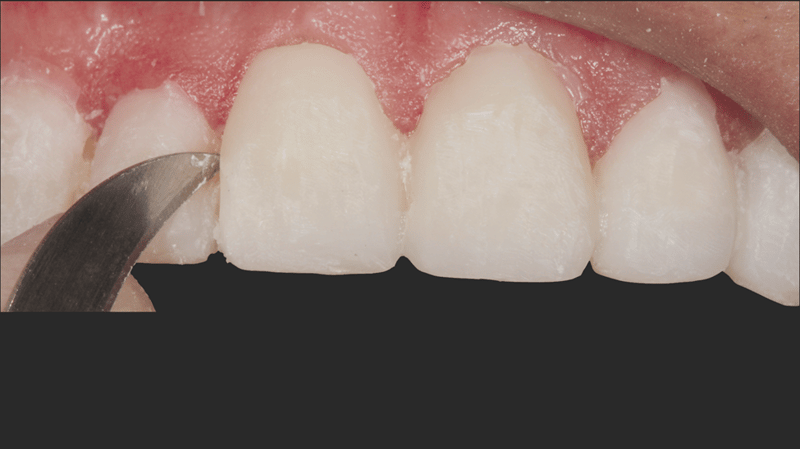

- Veneer Separation: A #12 blade and separating saw were used to carefully separate the veneers, ensuring precision.

- Gingival Sulcus Preparation: Ultrapak™ knitted cord Size #0 was packed into the gingival sulcus to prepare for etching.

- Etching Uncut Enamel: A 30-second etch was performed using Ultra-Etch 35% phosphoric acid on the uncut enamel.